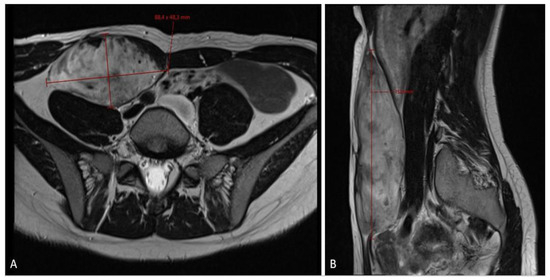

Figure 4.

An MRI scan ((A)—axial plane; (B)—sagittal plane) at the 6-month follow-up checkup showing tumor growth progression, sized 10.5 × 6.2 × 17.5 cm in craniocaudal diameter, located in the musculus rectus abdominis on the right side.